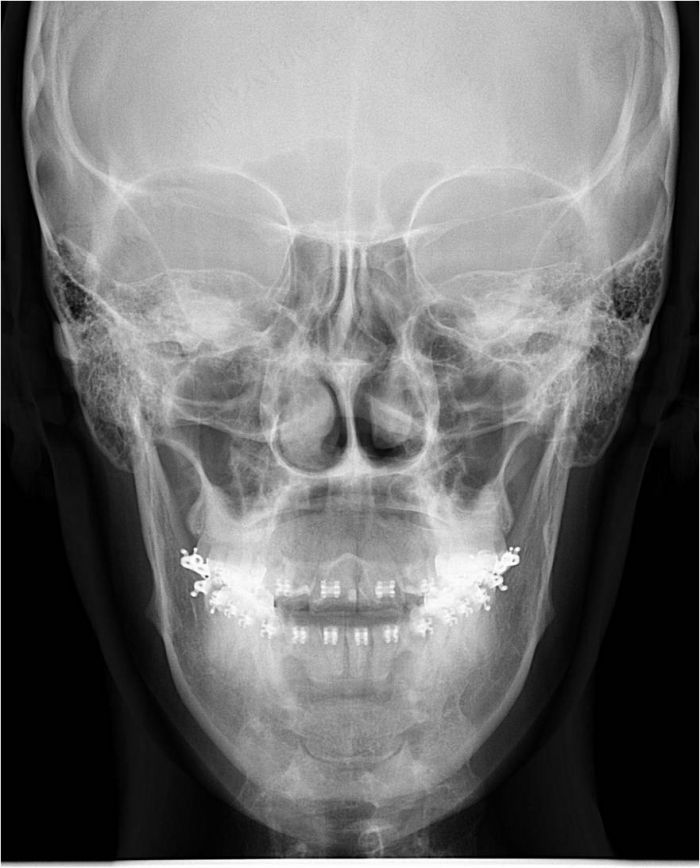

Telerradiografia frontal inicial

Telerradiografia frontal após a cirurgia